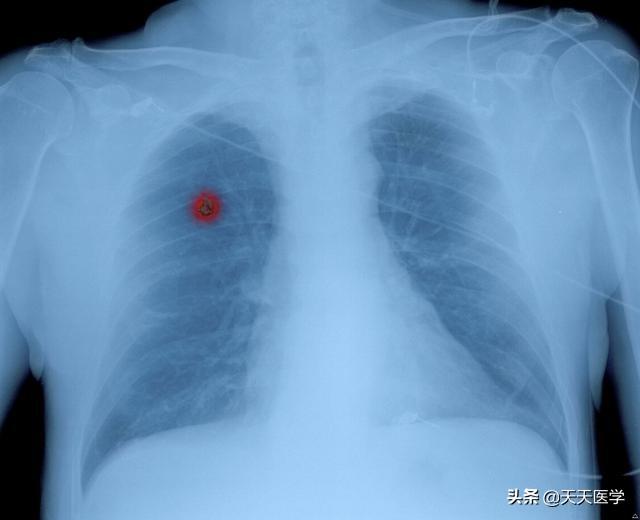

- Le scanner thoracique est actuellement la méthode de dépistage du cancer du poumon la plus efficace. Si l'examen par scanner thoracique révèle des nodules pulmonaires avec un signe lobaire, un signe de bavure, un signe vacuolaire, une image bronchique aérienne, une artère trophoblastique tumorale, une coupure vasculaire et un signe d'amas, une dépression pleurale ou un signe de traction, une cavité excentrique, une lésion ressemblant à du verre dépoli, une masse hilaire et d'autres signaux d'imagerie, le cancer du poumon est fondamentalement confirmé.

Les premiers symptômes du cancer du poumon sont classés en type périphérique (cancer survenant au bord du poumon) et en type central (cancer survenant dans les bronches près du hile) en raison des différentes localisations du cancer du poumon. Le cancer du poumon central se développe souvent dans la lumière bronchique, ce qui entraîne un rétrécissement de la lumière bronchique, une atélectasie ou une pneumonie obstructive, et des symptômes tels qu'une toux persistante, la présence de sang dans les expectorations, une oppression thoracique et un essoufflement.